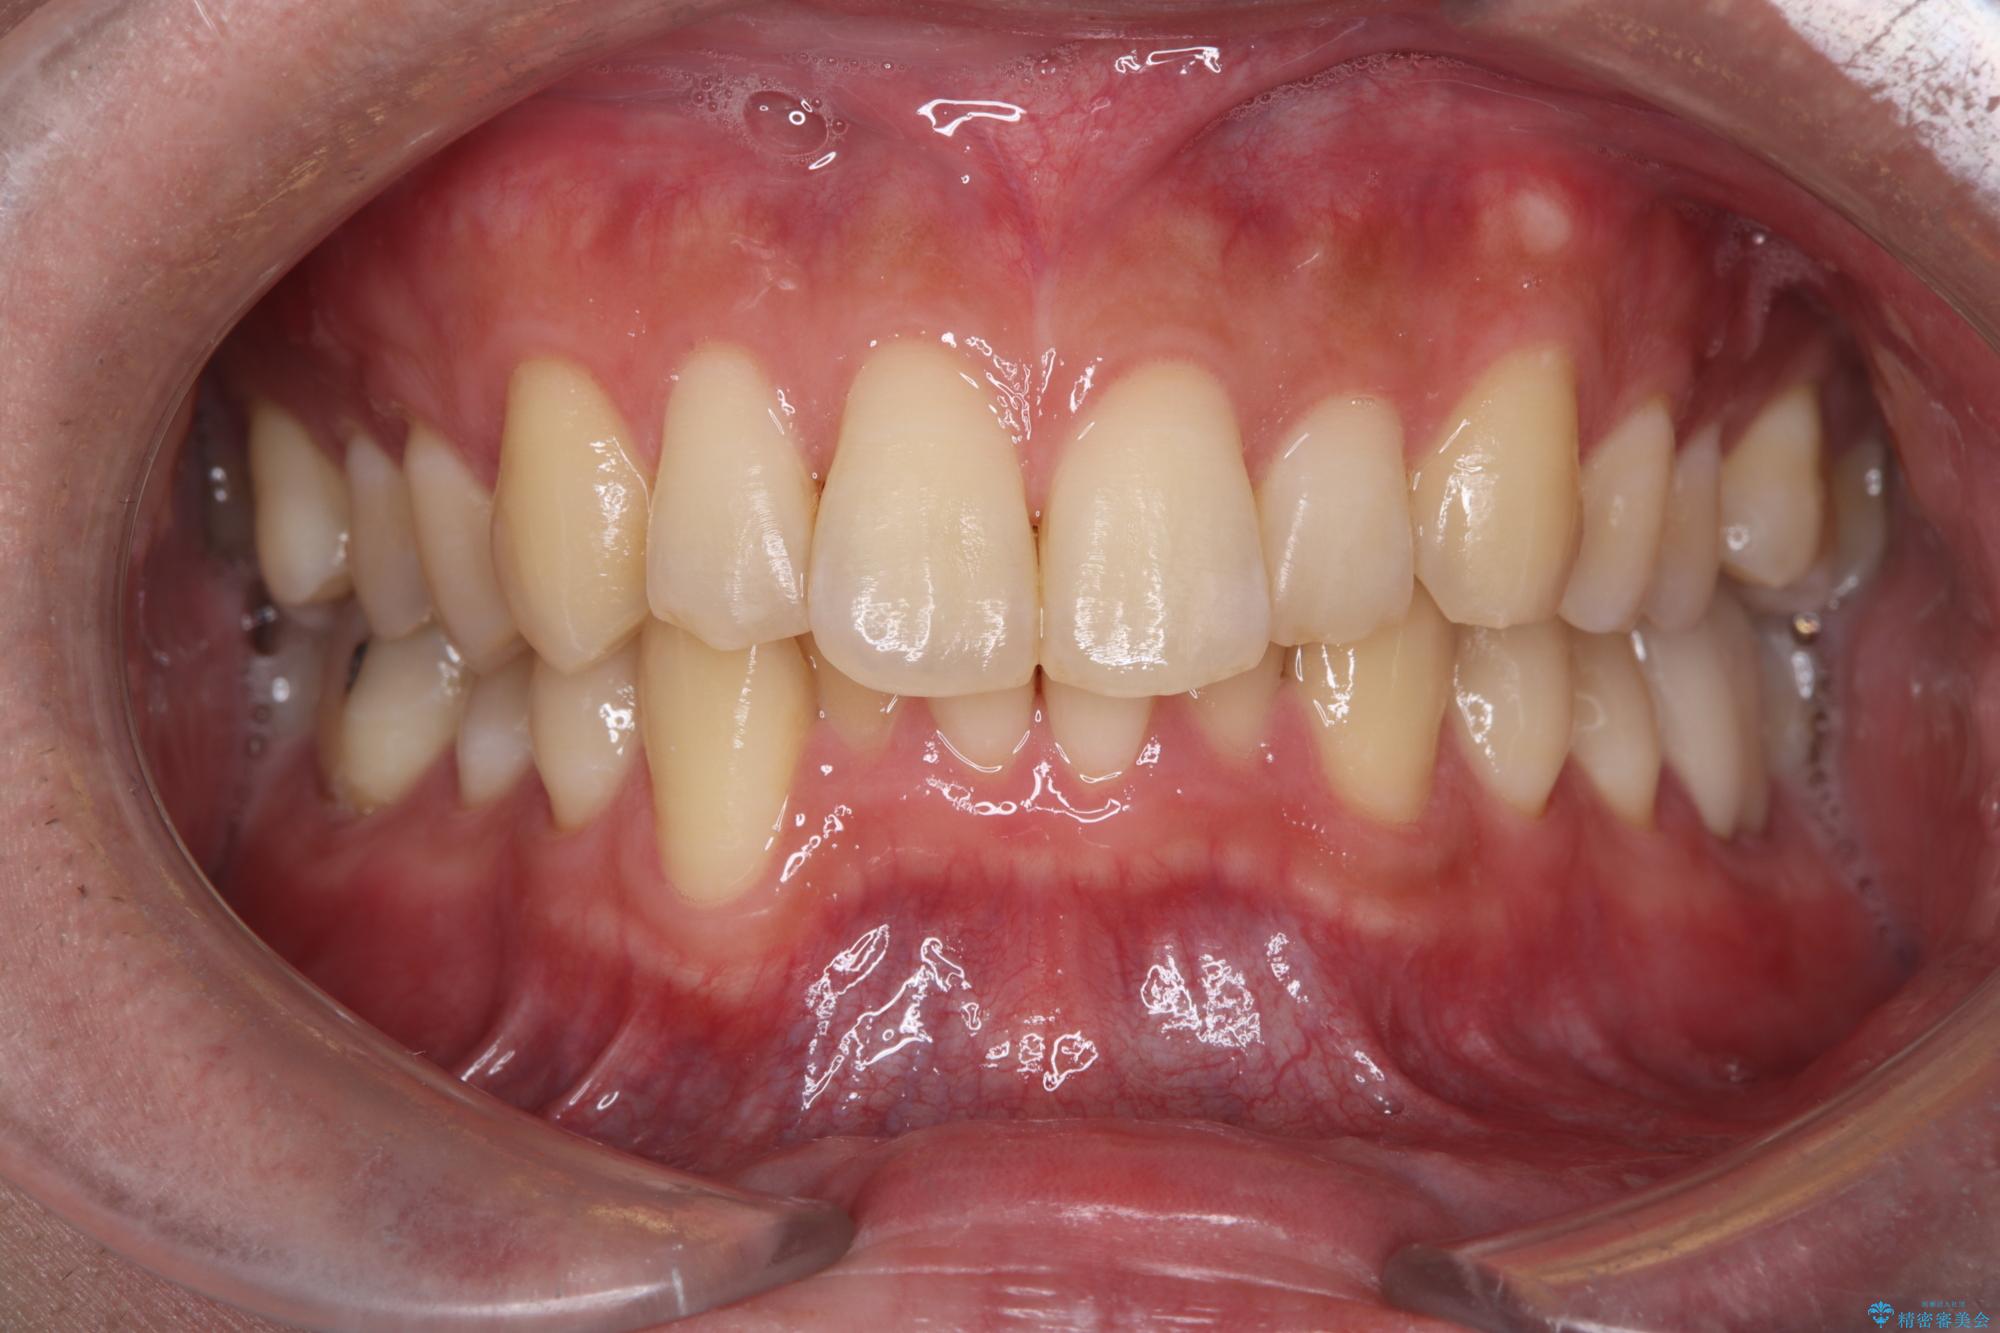

白い歯で清潔感get!初ホワイトニング

- 初めてのオフィスホワイトニングということで痛みなどの不安があったようですが、痛み等なくトーンアップし白くなりました。